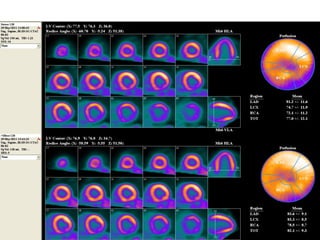

A 60-year-old male with multiple comorbid issues presented to the emergency room with chest pain. An ECG showed tall T waves and right bundle branch block. A CT/PET stress test revealed a small inferolateral infarct and significant peri-infarct ischemia. The patient was referred to cardiology to rule out acute coronary syndrome.